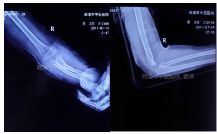

外院片如下:

简要病史:玩耍时跌倒致左肘部畸形、肿痛、活动受限,就诊于当地医院,拍片诊断为肱骨髁上骨折,转来我院。

治疗经过:入院行四步复位法手法整复,小夹板外固定